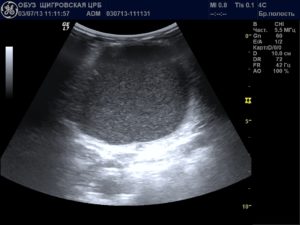

Вода, скопившаяся в позадиматочном пространстве, выявляется во время проведения ультразвукового исследования органов малого таза. Нынешнее оборудование позволяет с максимальной точностью определять её объём.

Жидкость позади матки можно обнаружить при проведении ультразвукового исследования. Чтобы уточнить природу ее происхождения, требуется провести пункцию. Ее делают во время лапароскопической операции.

Свободная жидкость в позадиматочном пространстве диагностируется с помощью УЗИ

С его помощью можно увидеть и распознать даже минимальное количество жидкости как в матке, так и позади нее. Визуально на экране ультразвукового аппарата скопление небольшого количества жидкости напоминает неширокую полоску темного цвета.

Ультразвуковое исследование является одним из самых доступных и достоверных методов, с помощью которого можно обнаружить даже небольшое содержание жидкости в полости малого таза.

На экране УЗ-сканера жидкостные образования за маткой выглядит черного или темно-серого цвета, чаще имеет форму узкой полоски, если ее количество небольшое.

При большом количестве она растекается между органами и принимает неправильную форму.

Точного количества жидкости за маткой в миллилитрах с помощью этого метода определить невозможно из-за того, что жидкость растекается между складками брюшины и органами и не принимает какой-то строгой формы. Тем не менее для описания количества жидкости на УЗИ в полости малого таза существуют определенные критерии.

Врач измеряет наибольшую длину вертикального уровня жидкости за маткой. Если высота уровня жидкости составляет до 10 мм, то ее количество считается незначительным.

Если высота уровня жидкости составляет от 10 мм до 50 мм, то количество ее считают умеренным, более 50 мм – значительным.